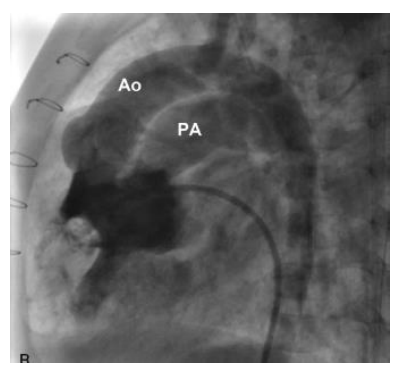

Os seguintes parâmetros foram obtidos:

- Condição basal: AD 13 mmHg / VD 50/18 mmHg / AP 50x35(47) mmHg / Capilar 16 mmHg / RVS 16 Woods / RVP 16,3 Woods.

- Condição após NO 40 ppm: AD 10mmHg / VD 56/16 mmHg / AP 57X20(37) mmHg / RVS 12 Woods / RVP 13 Woods.

(Legenda: AD: átrio direito; VD: ventrículo direito; AP: artéria pulmonar; RVS: resistência vascular sistêmica; RVP: resistência vascular pulmonar.)

Com base nessas informações, assinale a alternativa correta.